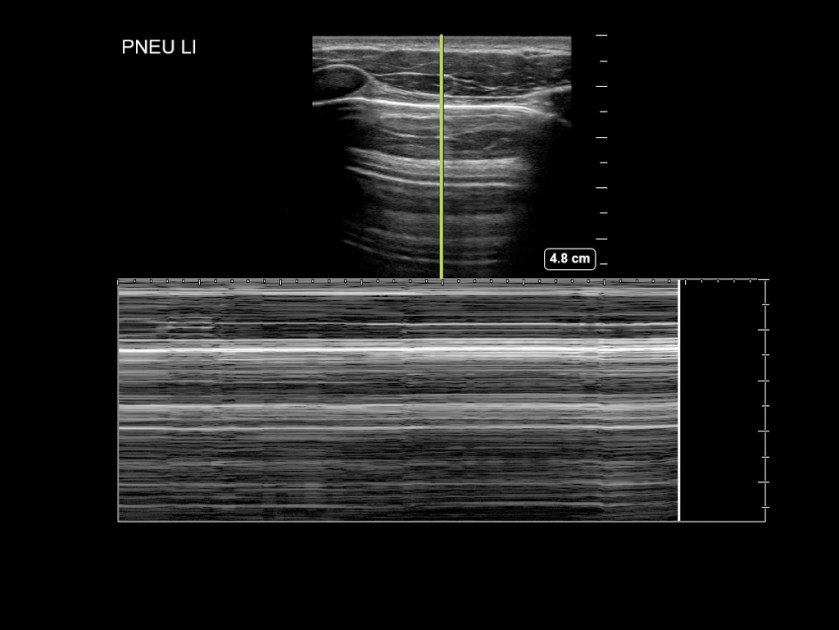

- Im M-Mode: ein Strahl wird durch das subkutane Gewebe, die Interkostalmuskulatur, Pleura und Lunge gelegt. Bei normalen Verhältnissen entsteht unterhalb der Pleuralinie ein granuliertes Muster, während im Bereich der Cutis, Subcutis und Interkostalmuskulatur ein lineares Muster entsteht („Seashore-Sign“). Bei Vorliegen eines Pneumothorax ist aufgrund der fehlenden Bewegung im Bereich der Pleuralinie ein durchgehend lineares Muster zu beobachten („Barcode-Sign“).